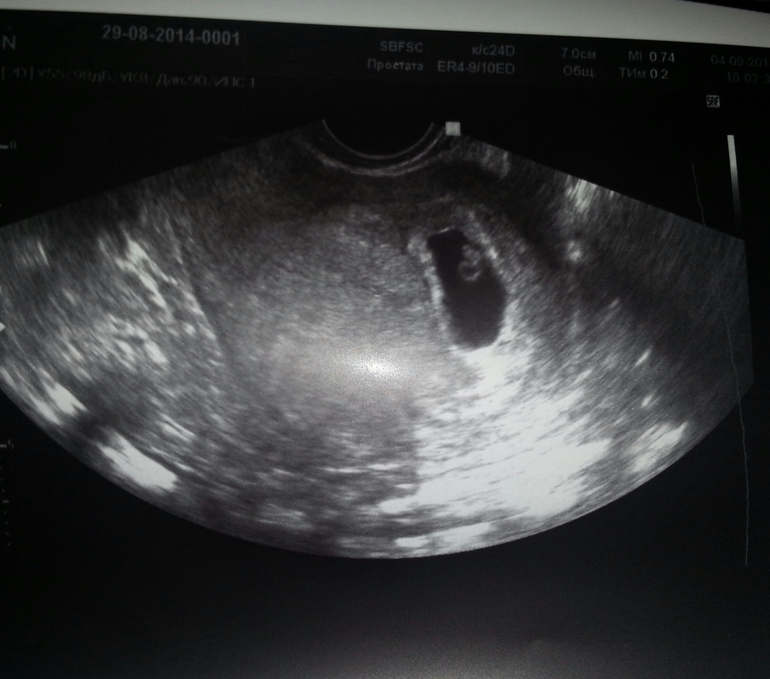

Результаты: УЗИ, КТГ, доплера, скринингаСлава Богу все хорошо! Это УЗИ успокоило меня) итак: ПЯ аж целых 21мм!!! КТР 4,2мм! Малюсечка))) но уже сердечко бьется!!! ЧСС 180 уд/мин! Кистозное ЖТ 30мм так и есть, но сказали, что к 10 неделям должно рассосаться! Ну вот и все)) я безмерно счастлива! Вот вроде недавно Стеша была 5мм)) и уже второй малыш растет!! Это не передать словами!! Ну и фото)

Лен, я такое узи еще ни когда не видела! Прям видно головку и хвостик)))) Хочешь сегодня посмотрю кто у тебя будет, сынок или доча?